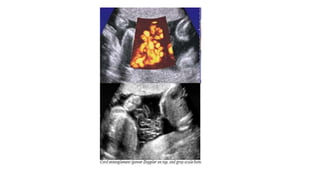

MONOCHORIONIC

MONOAMNIOTIC TWIN

Cord entanglement

MCMA twins almost always have umbilical cord entanglement when

visualised using colour flow Doppler. Such a finding has not consistently

been demonstrated to contribute to overall morbidity and mortality. [New

2016] (D)

MCMA twins have a high risk of fetal death and should be delivered by

caesarean section between 32+0 and 34+0 weeks. [New 2016] (D)